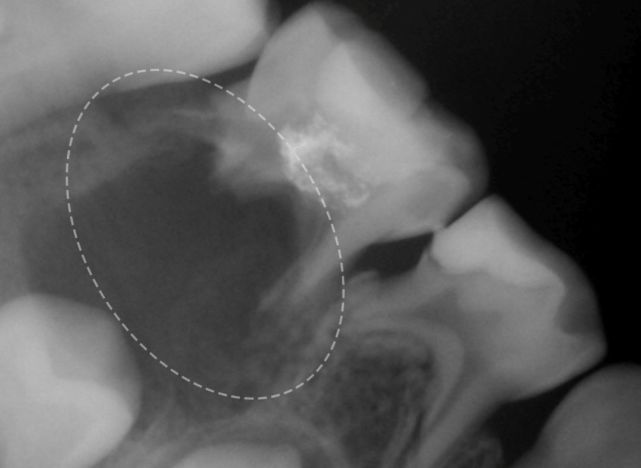

牙龈肿得像墨囊?

宝贝在长牙阶段,牙龈上有时会冒出来像染了墨水一样的包,把妈妈吓一跳。

这其实是新牙“破土而出”之前,血液、组织液在牙齿周围的空间内蓄积所致的,医学上称之为萌出性囊肿或血肿。

等到牙齿突破牙龈后,“墨囊”就自行消退了,也不需要治疗。如果牙齿过了2周还未萌出,或发生了感染,可以带孩子看诊齿科。